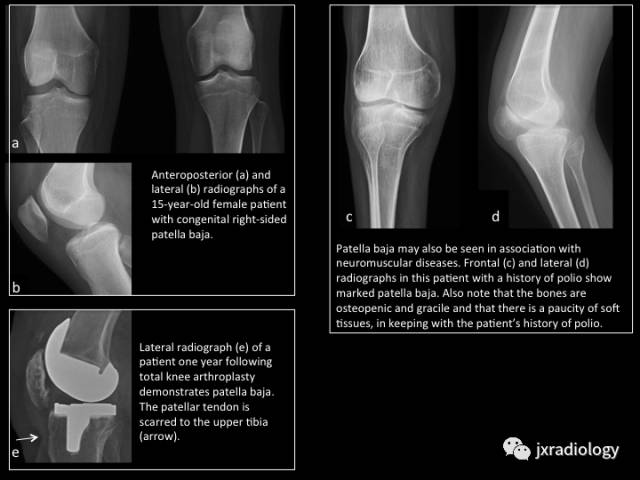

Fig. 8: Patella baja

图8:低位髌骨

a,b图,15岁女孩右膝先天性低位髌骨。

c,d图,低位髌骨也见于神经肌肉疾病;患者既往有脊髓灰质炎病史。

e图,人工膝关节置换后患者一年复查,侧位片提示低位髌骨;箭头是髌韧带疤痕形成。